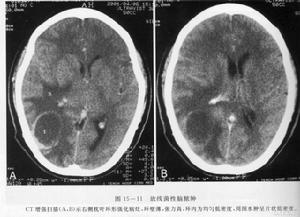

3.頭顱CT掃描和磁共振檢查可見囊腫顱骨片有囊壁鈣化影如合併胸肺型X線檢查可見肺部有明顯改變

4.顱骨片有囊壁鈣化影。頭顱CT掃描和磁共振檢查可見囊腫。

3.腦瘤型除頭痛,噁心,嘔吐等一般顱內壓增高症狀外,尚可有肢體運動障礙及顱 神經損害等定位體徵,可出現視乳頭水腫。腦脊液壓力增高,白細胞及蛋白可輕度增高。此型約相當於蟲體腦內時間較 長,形成較大的多房性囊腫肉芽腫。